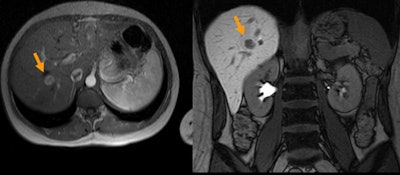

![]() |

| MRI (above) was equivocal in the diagnosis of a liver lesion. Volume CT perfusion imaging (below) revealed hyperenhancement suggesting focal nodular hyperplasia that was later confirmed by CT-guided biopsy. |